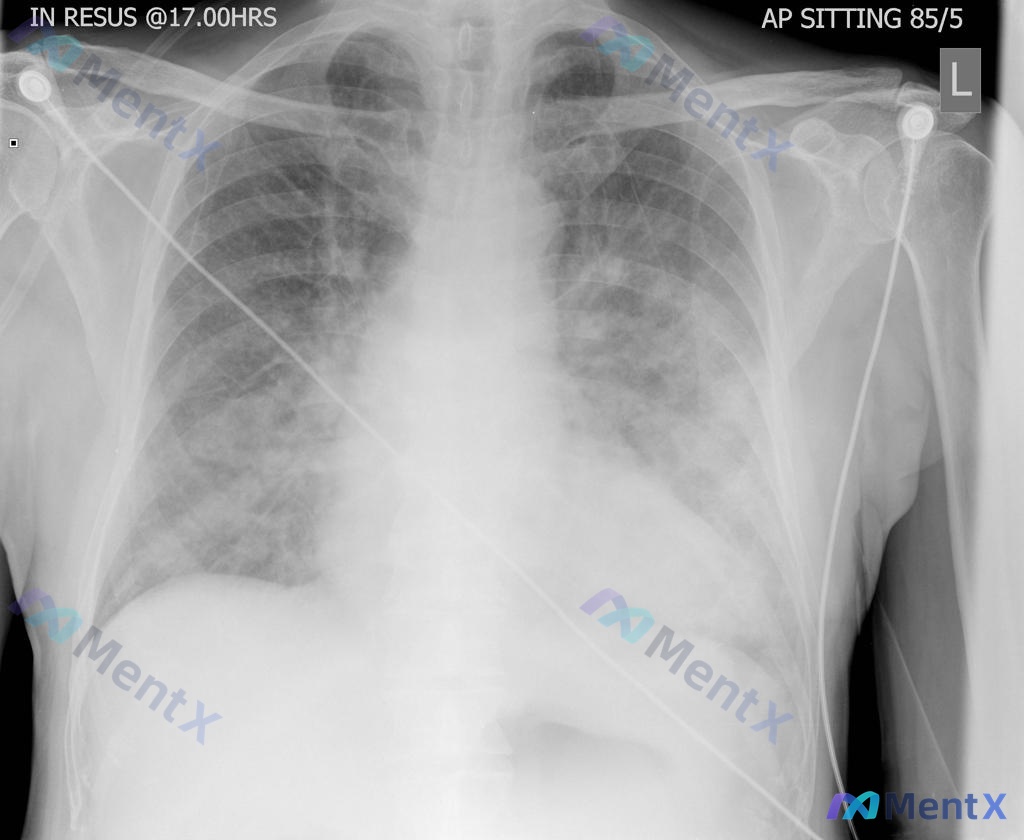

整理了一份急诊病例资料,几个点串起来很有意思,先抛出来看看大家的第一思路: - 69岁男性,既往有高血压、肥胖、糖尿病、GERD - 关键线索:自述已经几个月没有服用处方药了 - 此次因「睡着时突然出现呼吸困难」送急诊,呼吸急促但无手臂/下巴疼痛 - 后续出现「过去24小时几乎没有排尿」 目前有的初...